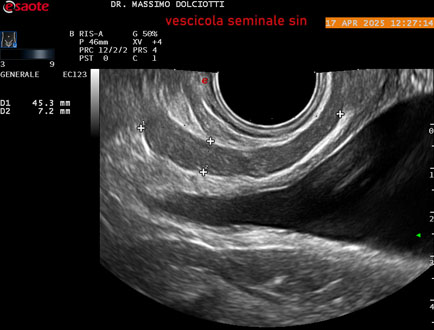

Data inserimento: 01/10/2025

Ecografia del: 17/04/2025

Strumento: Esaote MyLab Eight

Sonda: Convex Multifrequenza 1-8 MHz, Endocavitaria Multifrequenza 3-9 MHz e 3-13 MHz

Età Paziente: M 35 anni

Motivazione dell'esame: disuria.

Commento all'esame: le immagini ed il video documentano la prostata di ecostruttura regolare e morfovolumetria normale con diametro trasversale di 40 mm, diametro anteroposteriore di 21 mm e diametro longitudinale di 43 mm, con volume prostatico calcolato di 18 cc (v.n. < 20 cc), il profilo prostatico è regolare e netto, non si documentano calcificazioni intraghiandolari, la vascolarizzazione della ghiandola è normale. La vescicola seminale destra presenta diametro longitudinale di 44,4 x 7,8 mm, la vescicale seminale sinistra ha diametro longitudinale di 45,3 mm x 7,2 mm.

Conclusioni: prostata normale (normal prostate).